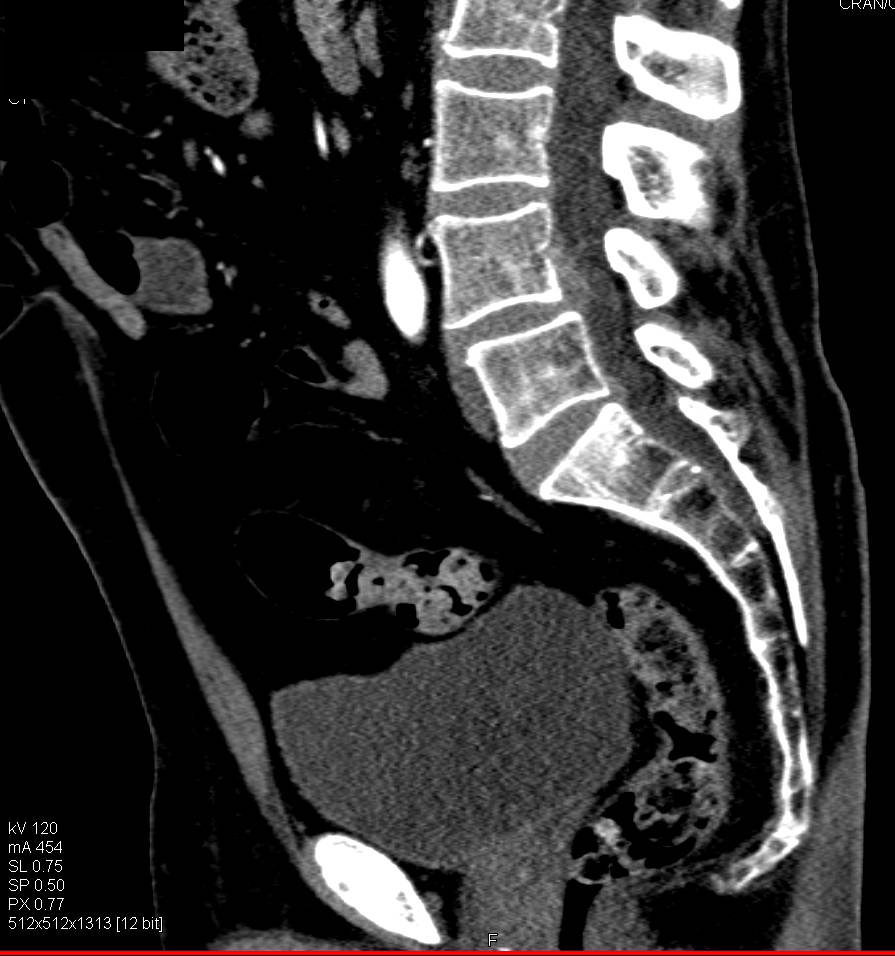

Right Renal Artery Stenosis